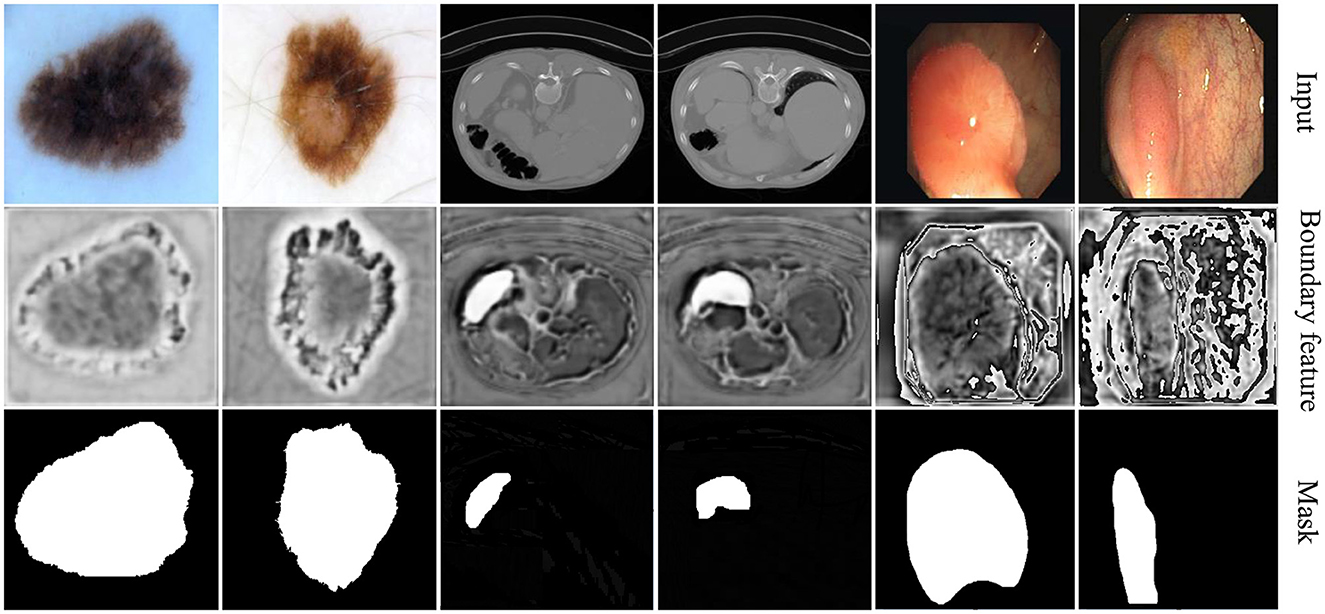

4.3.4.2 Visualization of boundary-aware features

The visualization results of boundary-aware features are presented in Figure 7. To illustrate the impact of boundary perception across different data modalities, we selected two representative cases from each dataset.

Figure 7

The first two columns showcase examples from skin lesion segmentation tasks, where the relatively uniform background enables rough localization of boundaries. Our method effectively enhances boundary contrast, aiding in precise delineation.

The middle two columns correspond to spleen segmentation on CT images, where the spleen is relatively small and absent in most slices. In this scenario, the boundary-aware decoder efficiently localizes segmentation areas, demonstrating its adaptability to challenging anatomical structures.

The last two columns display polyp segmentation cases, where polyps share similar textures with surrounding tissues. In this context, our method not only highlights polyp boundaries but also captures relevant contextual information, improving overall segmentation accuracy.

Compared to existing methods, our approach demonstrates superior boundary adherence in lesion segmentation, which is particularly beneficial for clinical applications requiring precise delineation. This improvement is driven by our novel feature fusion strategy, which enhances spatial consistency and effectively suppresses segmentation artifacts. By integrating multi-scale contextual cues, our model ensures sharper and more reliable boundary predictions, reinforcing its robustness across diverse medical imaging tasks.

These visualization results provide an intuitive understanding of boundary-aware features, revealing how boundary perception varies across different tasks and data modalities. This underscores the adaptability and diversity of model performance in various scenarios.